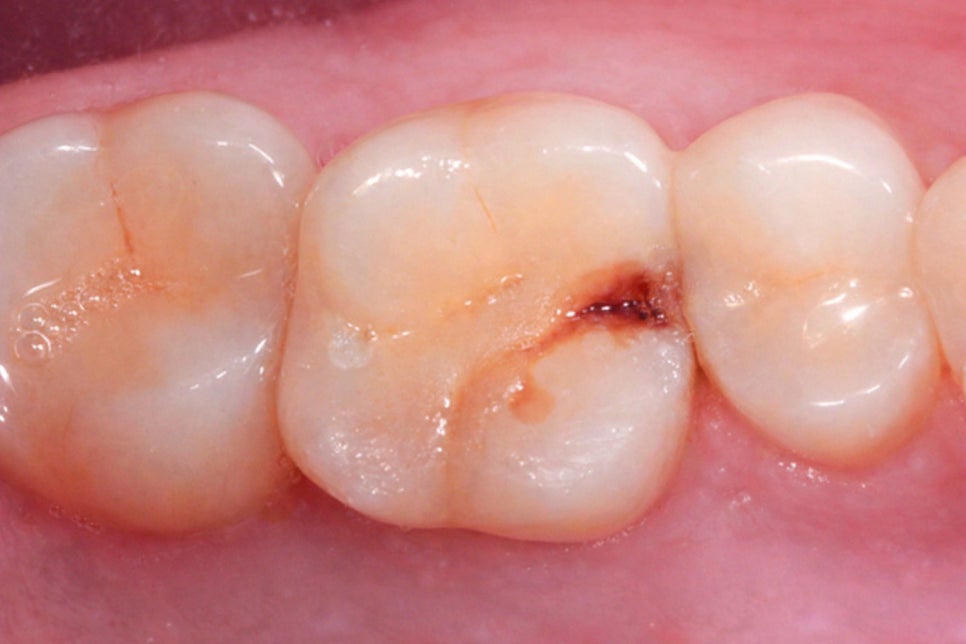

증상은 어떻게 될까?

제일 대표적인 증상은

특정 방향으로 음식을 먹을 때

느껴지는 날카롭고 순간적으로

나타나는 통증이 있습니다.

깨물었다가 떼는 순간에 찌릿하게 아프다가

금세 사라지는 것이 특징이며

찬 음식이나 음료에 시린 증상이 동반되기도 하며

어느 치아가 아픈지 정확히

알기 어려울 때도 많습니다.

따라서 당산 보존치과 는 미세현미경을 통해

육안으로는 확인하기 어려운

미세 균열까지 정밀하게 진단하는

과정이 이루어져야 된다 생각합니다.